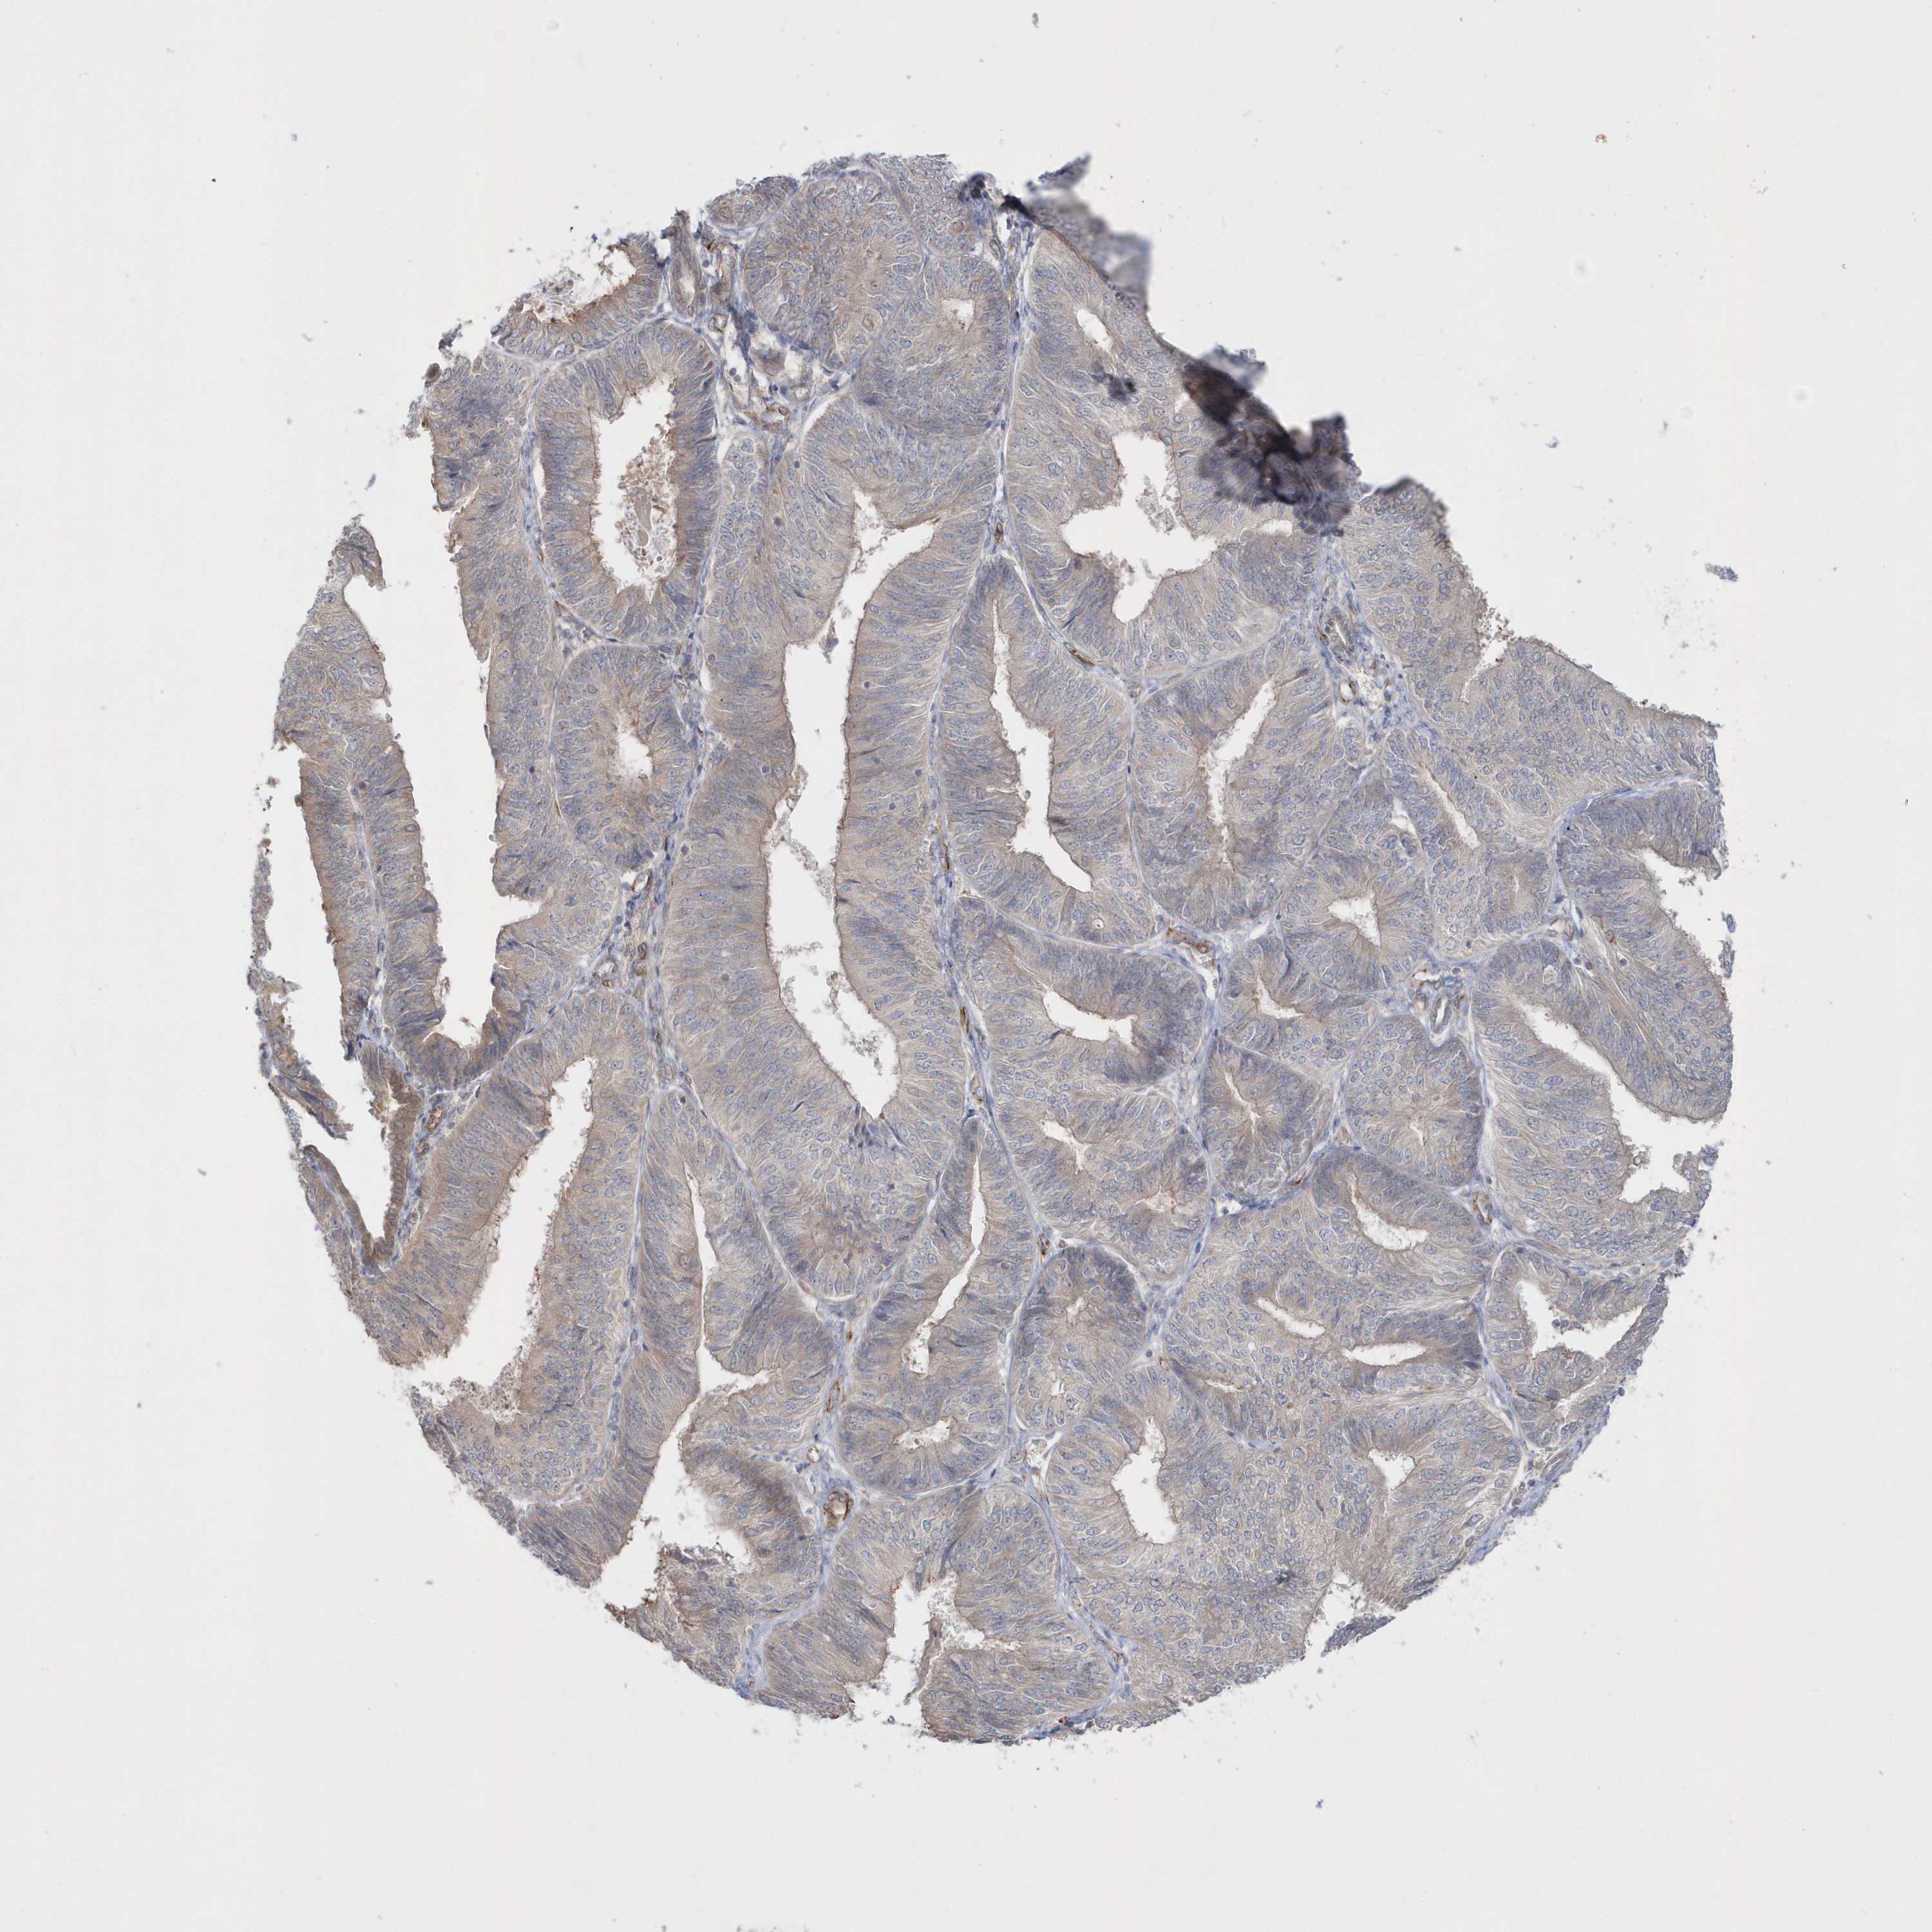

ENDOMETRIAL CANCER - Protein expressioni

A mouse-over function shows sample information and annotation data. Click on an image to view it in a full screen mode. Samples can be filtered based on level of antibody staining by selecting one or several of the following categories: high, medium, low and not detected. The assay and annotation is described here.

Note that samples used for immunohistochemistry by the Human Protein Atlas do not correspond to samples in the TCGA dataset.

Antibody stainingi

Antibody staining in the annotated cell types in the current human tissue is reported as not detected, low, medium, or high, based on conventional immunohistochemistry profiling in selected tissues. This score is based on the combination of the staining intensity and fraction of stained cells.

Each image is clickable and will lead to virtual microscopy that enables deeper exploration of all samples and also displays staining intensity scores, fraction scores and subcellular localization as well as patient and tissue information for each sample.

Antibody HPA036160

Staining

High

Medium

Low

Not detected

Intensity

Strong

Moderate

Weak

Negative

Quantity

>75%

75%-25%

<25%

None

Location

Nuclear

Cytoplasmic/membranous

Cytoplasmic/membranous,nuclear

Adenocarcinoma, NOS